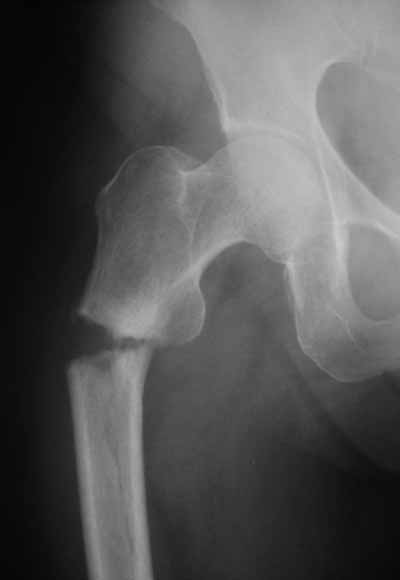

> Здравствуйте коллеги ! Прооперировали женщину 72 лет с Диагнозом: Чрезвертельный перелом

> левого бедра. Первый раз поставили PFN A (SYNTHES) см R-gr.

Присоединяюсь. Хотя посмотреть бы вторую проекцию.

И по фасу - шеечый винт можно бы и подлиннее.

Да? Качество рентгенограмм конечно неочень, но ведь это нестабильный перелом 31.А2.2, не так ли?